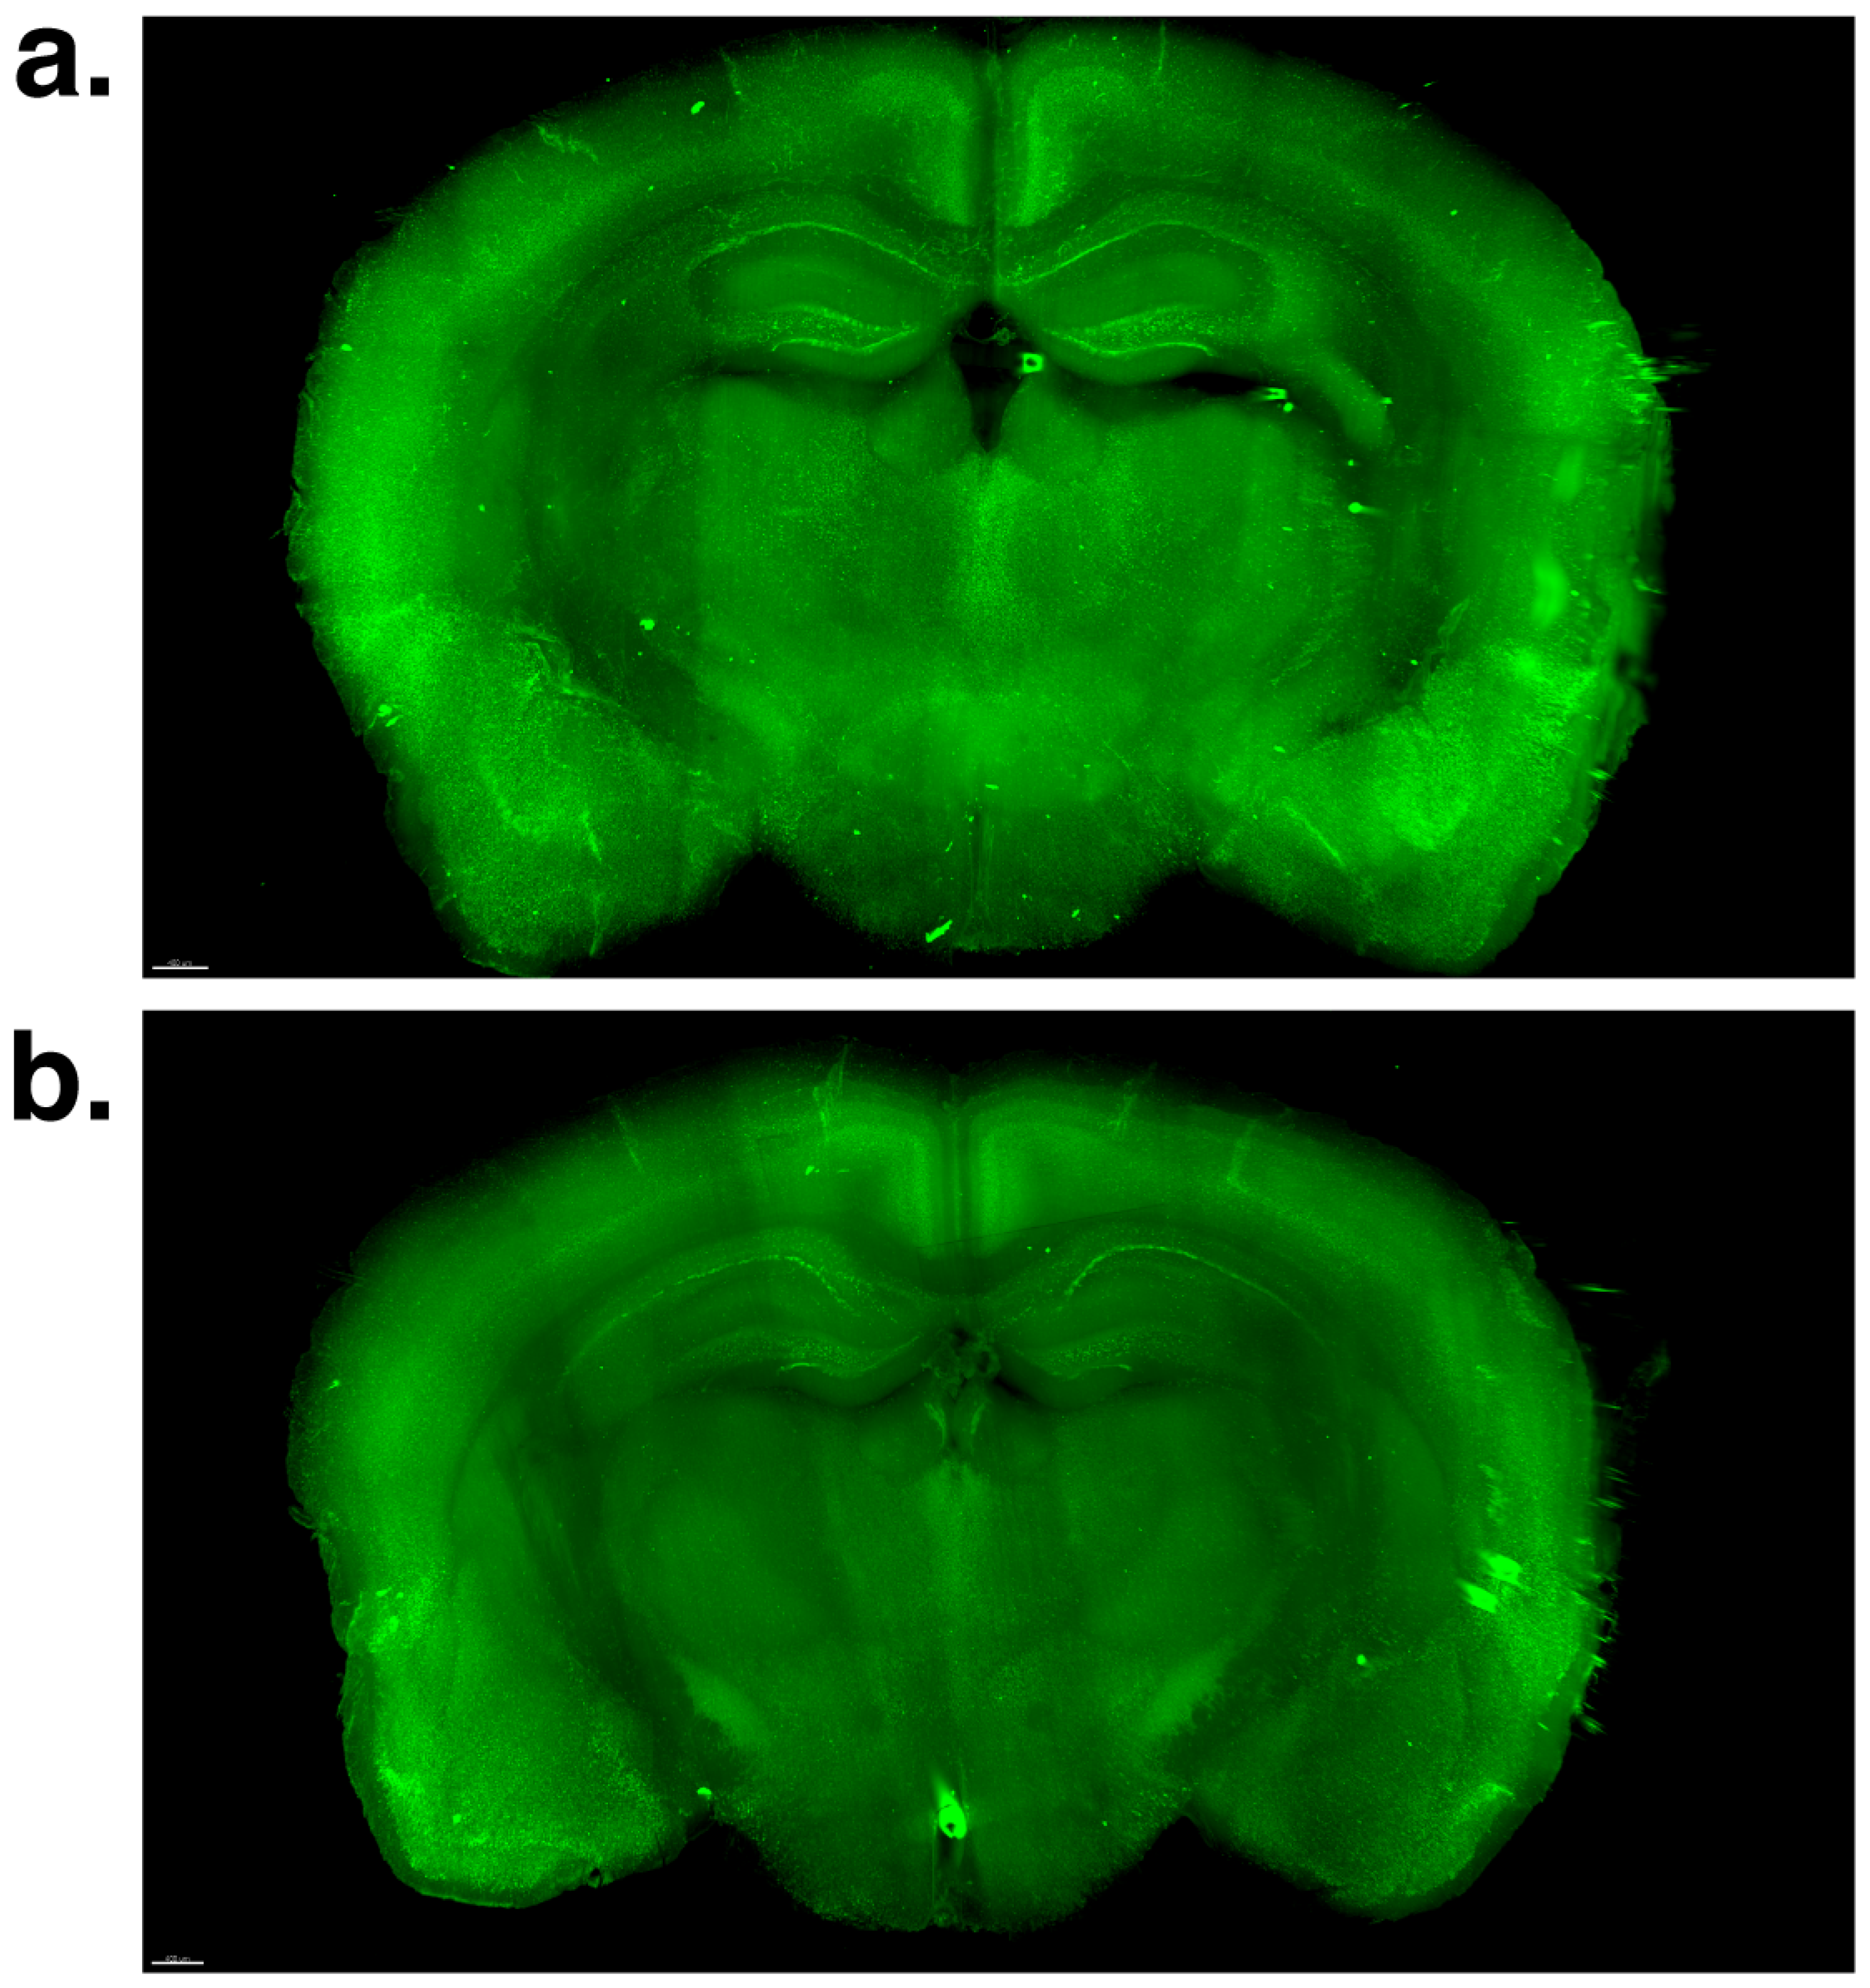

2.2. Effect of Voluntary Swimming on Total β-Amyloid Load and 3D Morphological Features in Brain Macro-LSFM Imaging